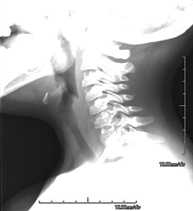

- Cervical spine X-ray

This technique uses X-ray rendered imaging for examining the cervical spine. Indicated for: trauma, cervical contracture, joint pain.

This technique uses X-ray rendered imaging for examining the cervical spine. Indicated for: trauma, cervical pain.